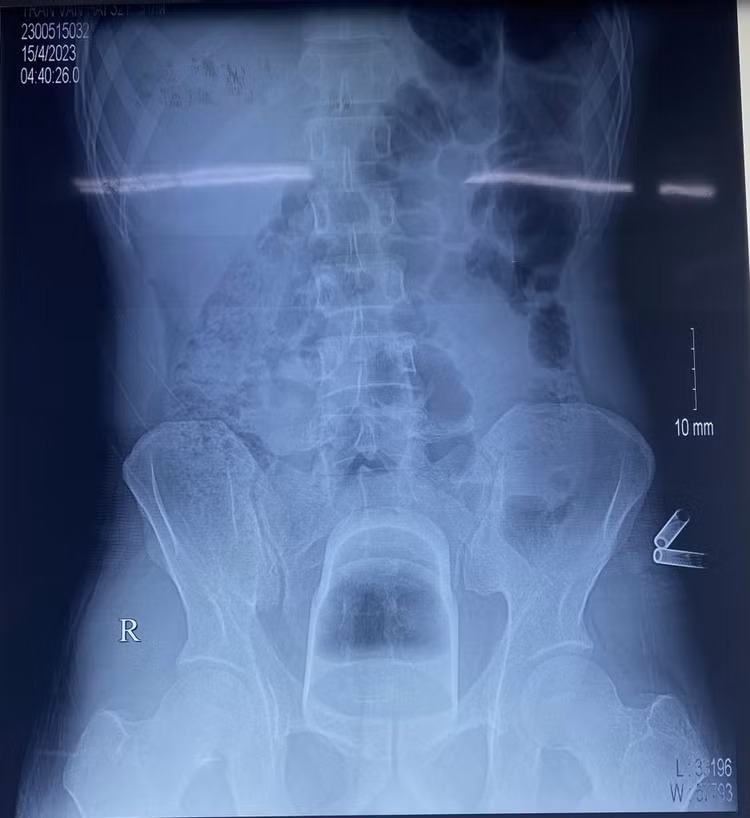

Bệnh nhân vào viện trong tình trạng tỉnh; mạch, huyết áp ổn định; không sốt, không nôn, bụng chướng. Phim chụp X-quang phát hiện dị vật nằm sâu trong trực tràng của bệnh nhân.

Phim chụp X-quang xác định một chiếc cốc mắc kẹt ở sâu trong trực tràng bệnh nhânPhim chụp X-quang xác định một chiếc cốc mắc kẹt ở sâu trong trực tràng bệnh nhân